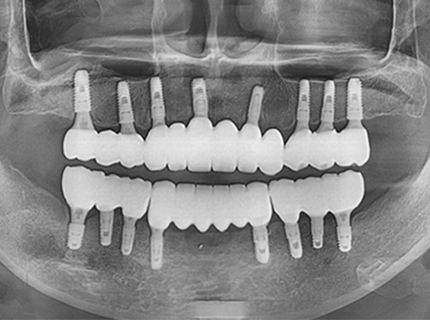

플라즈마를 활용해 임플란트 티타늄 표면의 친수성을 활성화하는 장비로,

임플란트 수술 전 단 40초 만에 표면 활성화 처리 및 멸균이 가능하여

최적의 상태로 수술이 가능합니다.

안전하고 빠르게 임플란트와 뼈의 융합 강도를 측정함으로써

정확하고 안전하게 보철물 체결 시기를 파악할 수 있는

임프란트 결합 강도 측정기를 사용합니다.